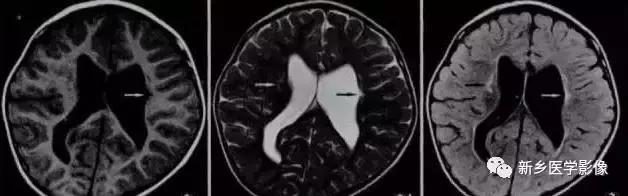

6.脑室周围白质软化症

主要与缺血缺氧及感染有关。

常见于早产儿。常见于早产儿的原因与胚胎期脑部损害发生的时间有关,胚胎早中期脑损害主要引发发育畸形,晚期主要引起脑血管改变。

由于脑室周围白质的血供分别来自脑室区和远脑室区的终动脉,未成熟儿终动脉深穿支的侧支循环尚未建立,而胚胎晚期脑室周围白质对缺血缺氧敏感。所以,脑室周围白质软化症多见于早产儿。

由于侧脑室周围有软化萎缩,故扩大的侧脑室外缘常不规则,不光整,这种不规则、不光整是本病引起脑室扩大的特征,另外,本病均表现有脑白质量减少及脑白质内斑片状软化病灶,脑白质减少严重时表现为部分区域白质消失,脑皮层与脑室侧缘接近甚至相连。CT表现为斑片状低密度灶。MR T1WI上呈低信号,T2WI呈高信号。